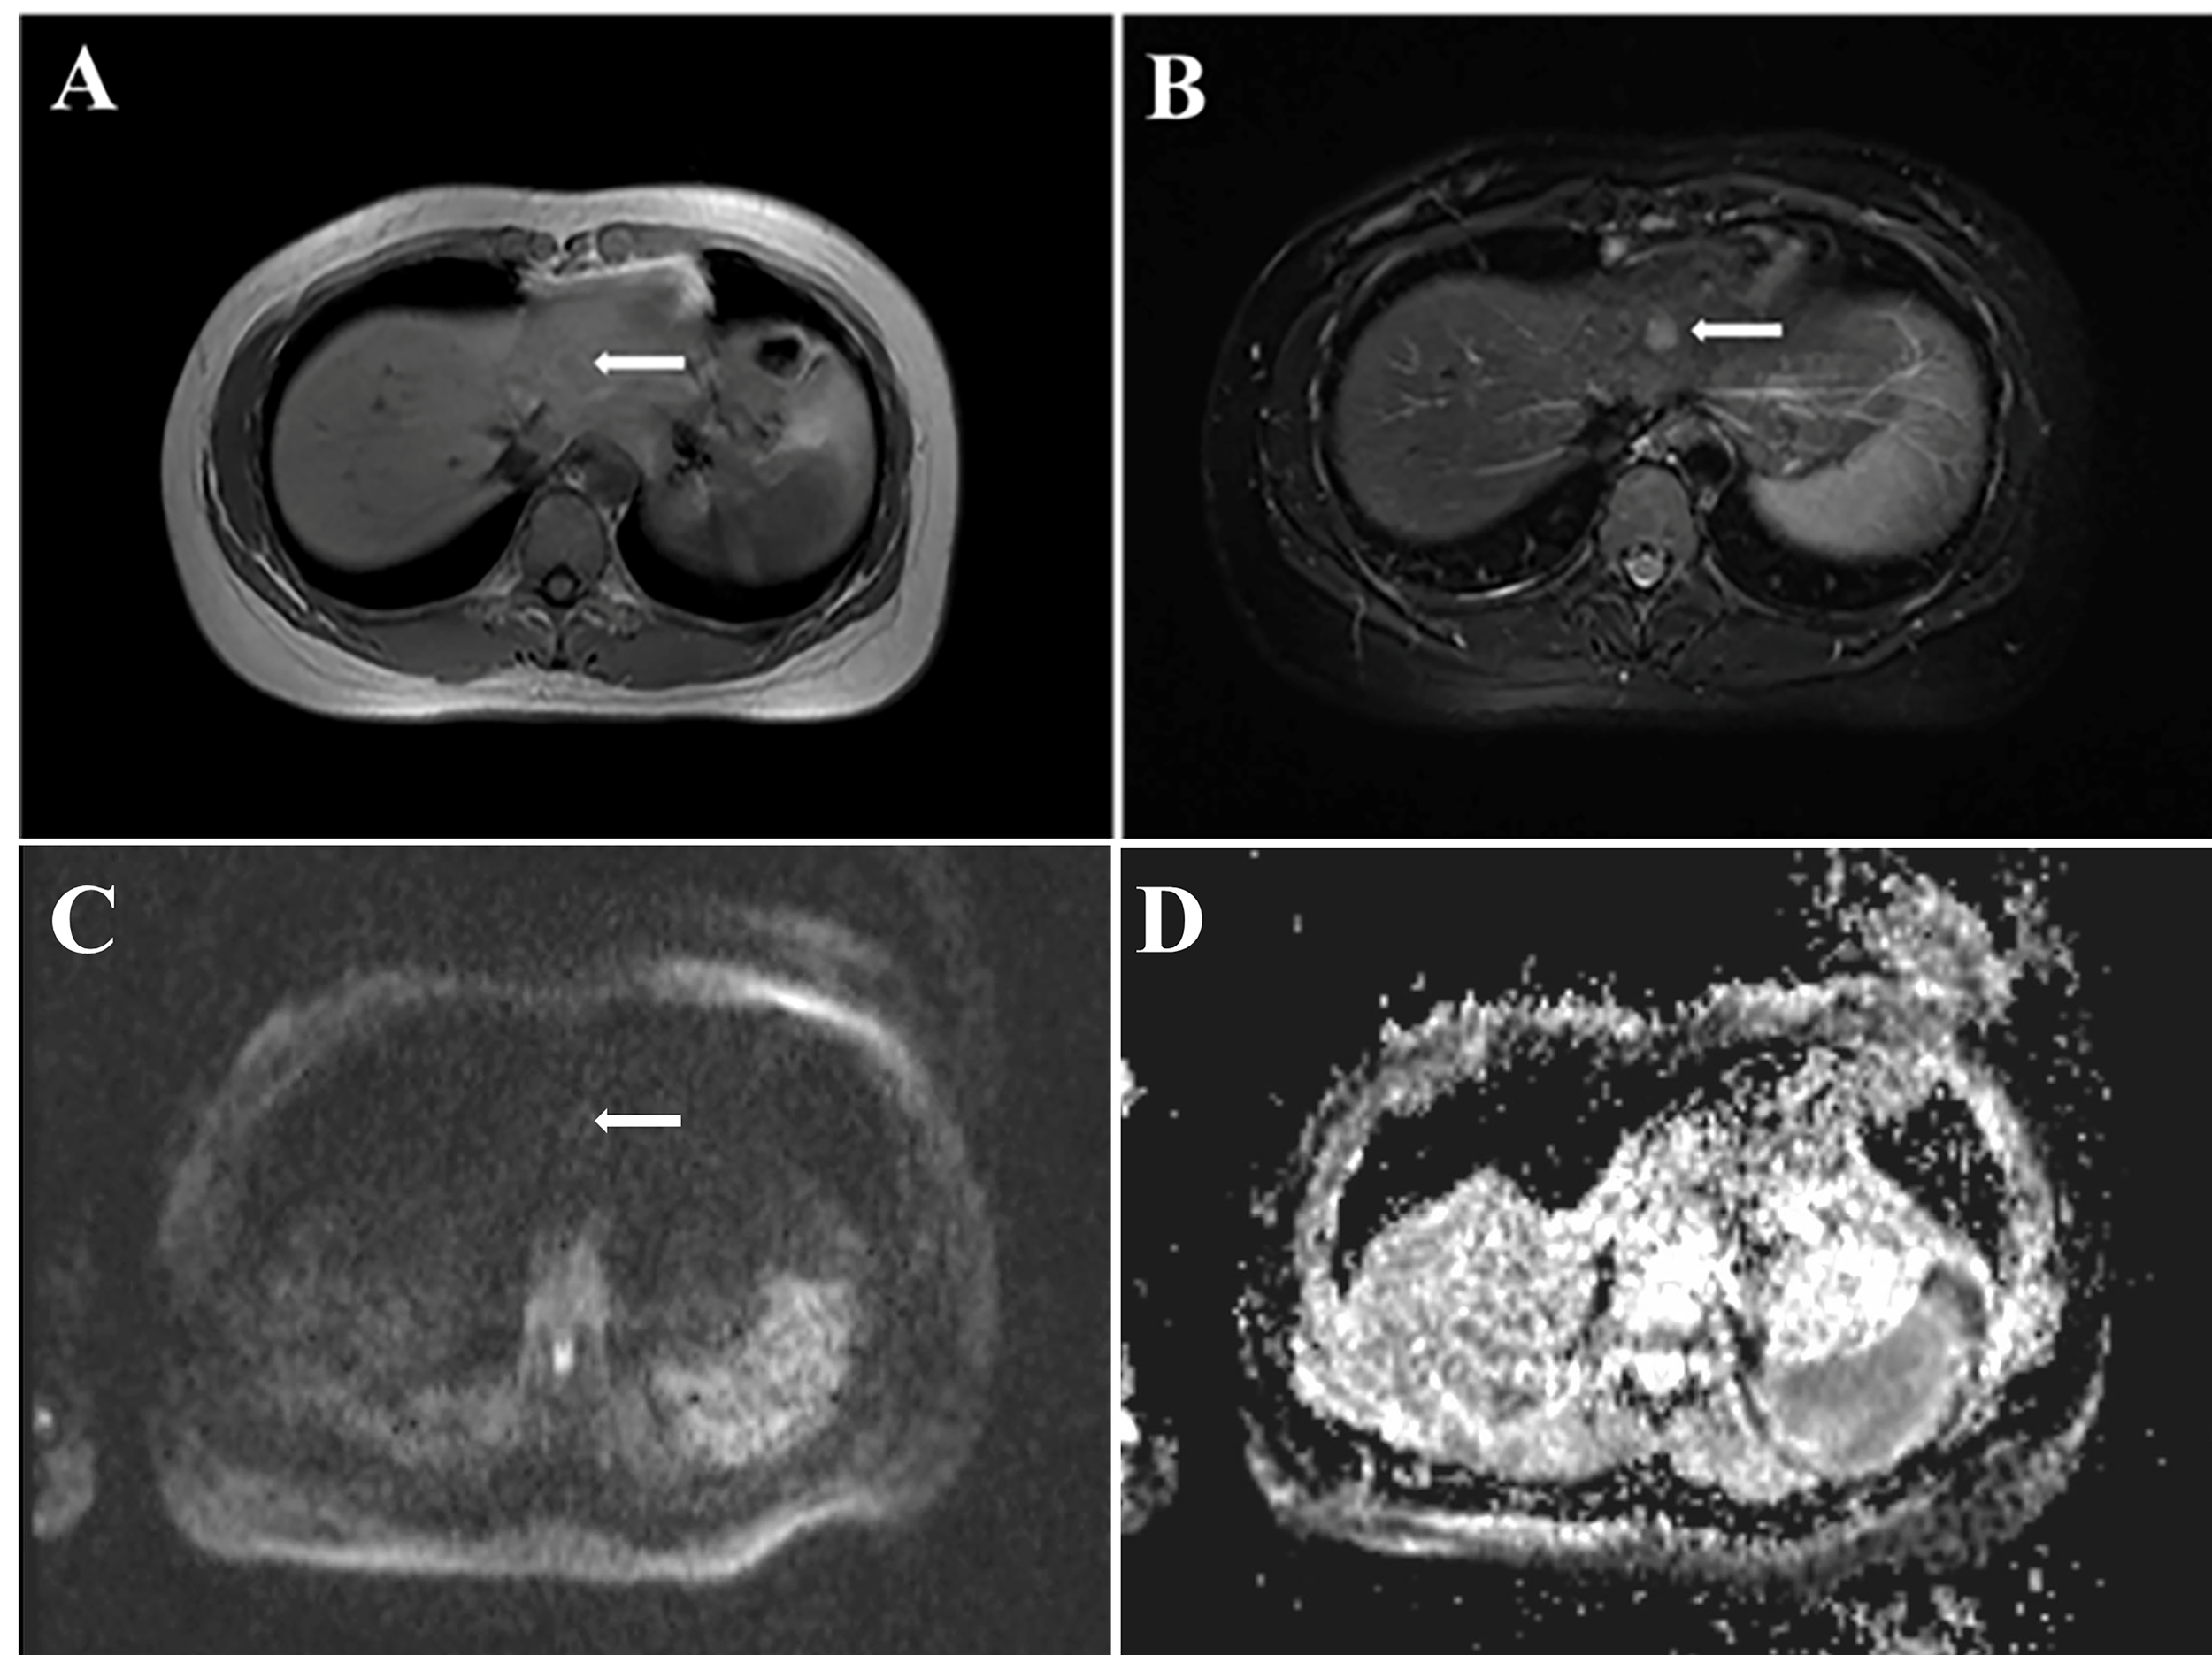

A 32-year-old Chinese female was admitted to Sichuan University West China Hospital with a 6-month history of upper abdominal pain. She denied previous radiotherapy or industrial chemical exposure. She had one previous pregnancy and and gave birth to a boy. In addition, she denied previous hormonal treatments and contraceptives. She was found to have viral hepatitis B for 6 years and had not received any treatment. Besides, she was healthy with no relevant medical or family history of diseases, such as hypertension or diabetes, and no history of smoking or alcohol consumption. Physical examination was unremarkable. A blood count showed Hb 14.2 g/dl (13–17.5), white blood cells 7.12×109/L (3.5-9.5), platelets 249×109/L (100–300), total bilirubin 12.5 umol/L (5.0-28), and AST 35 IU/L (<50). Serological testing for tumor marker of carcinoembryonic antigen (CEA) was 5.54 ng/ml (CEA ≥ 3.4 ng/ml was defined as abnormal) and hepatitis B surface antigen (HBsAg) was positive. The hepatitis B virus DNA (HBV-DNA) was less than 1×102 IU/ml (HBV-DNA ≥ 1×102 IU/ml was defined as HBV infection active), suggesting that HBV infection was inactive. The cancer antigen19-9 (CA19-9 ≥ 30 U/ml was defined as abnormal), CA125 (CA125 ≥ 24 U/ml was defined as abnormal) and α-fetoprotein (AFP≥ 7 ng/ml was defined as abnormal) was 25.6 U/ml, 13.3U/ml and 3.37, respectively. Abdominal computed tomography (CT) showed the lesion in the left lobe of liver was detected, and no tumor was detected in any other organs (Figure 1). Magnetic resonance imaging (MRI) of the upper abdomen was performed in our hospital for further diagnosis. The MRI showed a 1.1×1.3 cm lesion in the left lobe of liver, appearing low signal intensity on T1-weighted images and high signal intensity on T2-weighted images (Figure 2). Due to the similar appearance, hepatocellular carcinoma (HCC) was considered for preoperative diagnosis. The patient eventually underwent a laparoscopic liver resection of the left lobe. Macroscopically, the tumor was a yellowish solid mass with a diameter of 12mm. Microscopically, the lesion composed of undifferentiated epithelial cells with some atypical glands, and significant lymphocytic infiltration (Figure 3A). The epithelial tumor cells were featured by eosinophilic cytoplasm with large nuclei and prominent nucleoli. EBVencoded RNA (EBER) in situ hybridization was positive in tumor tissues. In addition, immunohistochemical analysis showed the lymphatic tissue positive for CD20 (B-cells, Figure 3B), CD3 (T-cells, Figure 3C), Ki-67 and negative for IgG4. Meanwhile, tumor cells positive for CK7 (Figure 3D), and negative for CK20, supporting the diagnosis of LEL-ICC.

FIGURE 3

Figure 3 Pathological examination and immunohistochemical staining. (A) Tumor was composed of undifferentiated epithelial cells with some atypical glands, and significant lymphocytic infiltration (HE stain, ×20); (B, C) Lymphatic tissue positive for CD20 (B-cells, B, ×20), CD3 (T-cells, C, ×20); (D) tumor cells positive for CK7 (immunostaining, ×20).